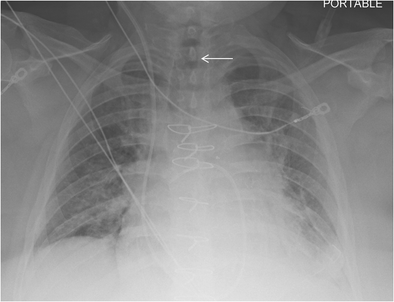

figure 6

Follow-up chest radiograph on the same patient after ET tube has been removed. The white arrow depicts the absence of the ET tube